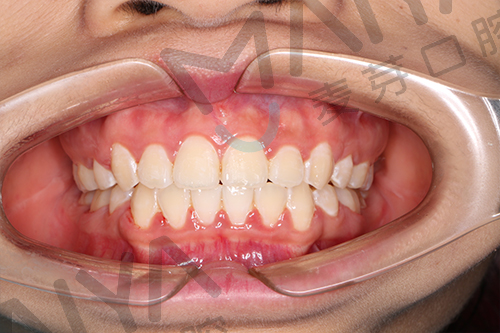

矫正过程中口内照

为她接诊的是麦芽口腔正畸专家张超主任,同时他也是国内首批无托槽隐形矫正的授权医师,张超主任看到何小姐的情况,发现由于之前的医生未对其矫正阶段进行准确判断,牵拉过早、频繁加力、力度过大,造成牙齿矫正力度外溢,造成了牙齿的外凸,同时对何小姐的脸型也造成了一定的影响。